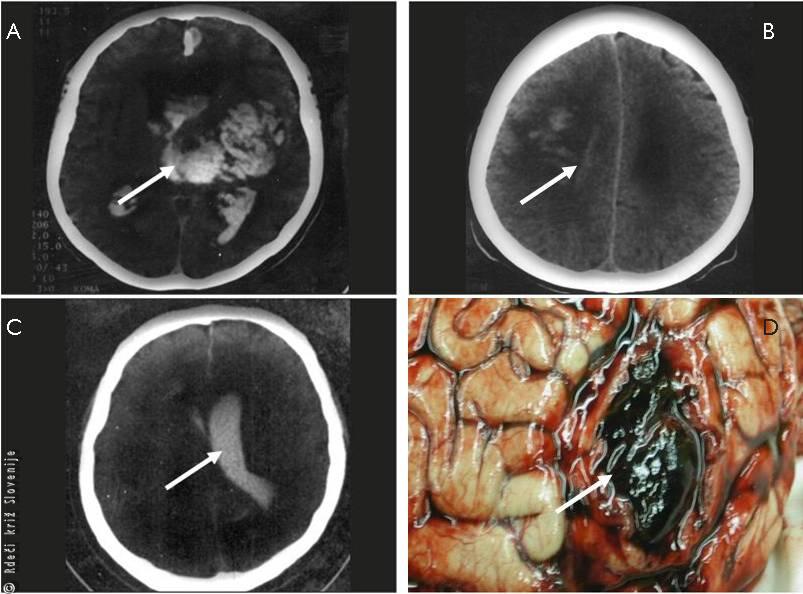

Slika 4

Globinsko slikanje znotrajmožganske krvavitve (izliva krvi v možgane zaradi razpoka manjše arterije).

A – Obsežna krvavitev, ki takoj privede do izgube zavesti.

B – Manjša krvavitev, ki praviloma ne povzroči izgube zavesti, prizadeta pa je ena polovica telesa in lahko dar govora.

C – Krvavitev v možganske votline (možganski ventrikli), ki hitro lahko privede do izgube zavesti, ponavadi pa ni prizadetosti po eni polovici telesa ali daru govora, če je bolnik še pri zavesti. Prisoten je močan glavobol, lahko otrpel vrat.

D – Znotrajmožganska krvavitev, ki jo prikaže obdukcija.